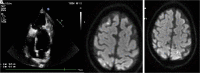

Huge Pseudoaneursym Presenting with Silent Myocardial Infarction and Stroke